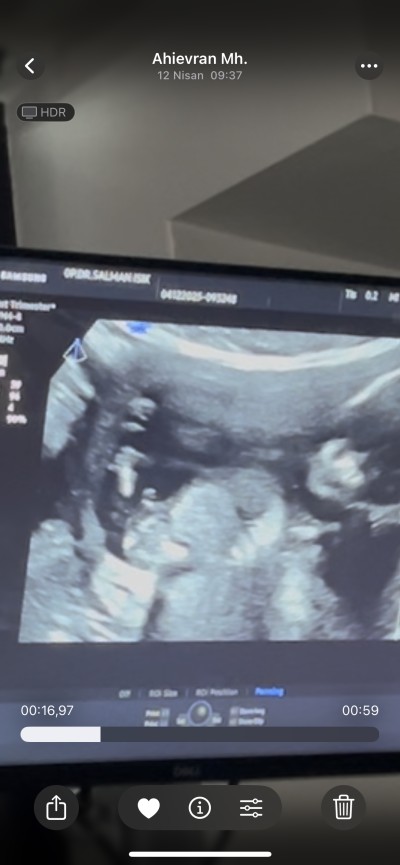

Cinsiyeti hala öğrenemedim kızlar bu 14 haftalıktı bugün 17 oldu devlete gittim o da çok hareketli suan net göremıyorum dedi ben video çekmiştim o görsek de çıkıntı var ama pipi mi başka bişey mi anlamadım

Canım o işretlediğin yer  bacak arasımu arasıysa eğer pipi görünüyor özeller söylüyor aslında cinsiyeti ben 12 de gittiğimde benimkininde bacak arası böyleydi doktorum erkek dedi

Yarın kesin öğrenicem canım ama tahminim yüzde yüz erkek diyor çünkü ultrosonda aynı senin ki gibi belliydi  pipi görünüyordu